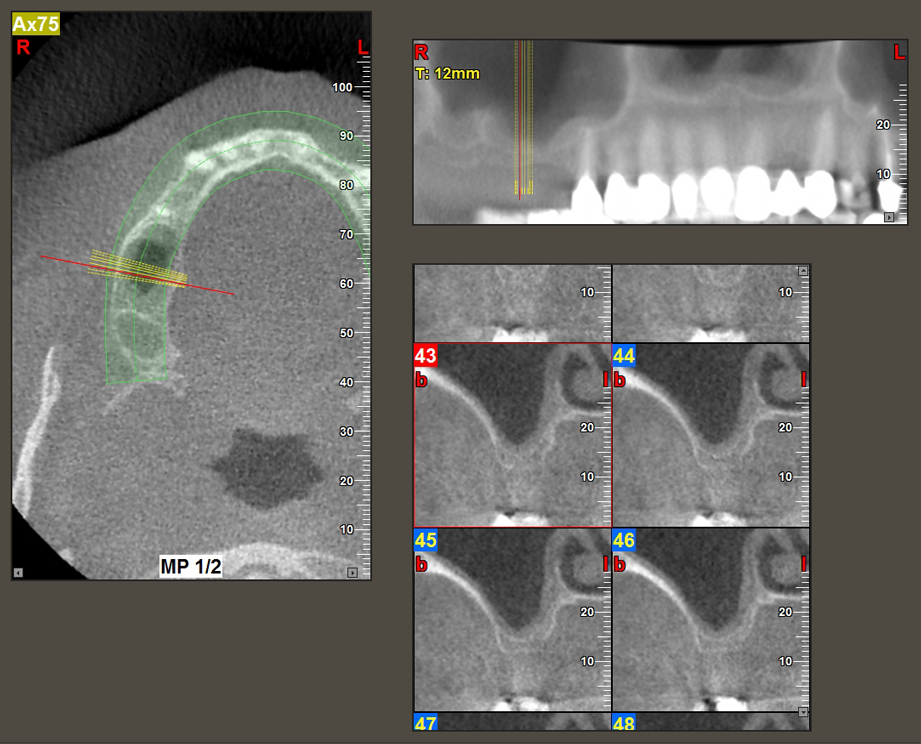

A 49-year-old female patient, a non-smoker and with nothing remarkable in her general medical history, was referred to our oral surgery practice for surgical extraction of tooth 16 and subsequent implantation. After the extraction, the patient experienced mild sinusitis trouble with the resultthat we initially waited six months before carrying out the measure. The residual bone height at the planned implant position measured 3-4 mm (Fig. 1 and 2).

Following atraumatic preparation of the mucoperiosteal flap, the implant position was marked with the I1 instrument and the site prepared – until initial resistance was felt. Piezosurgical instruments were used in an up and down movement without any pressure being exerted. The piezoelectric vibration produced the desired and efficient cavitation.

The I2A instrument (diameter 2.0 mm) was then used to perforate the sinus floor intermittently and on the smallest scale possible. This special piezosurgical method ensures that the Schneiderian membrane is not damaged. When the Z25P was used, the membrane was already lifted slightly by the coolant supplied via the instrument tip (Fig. 3). The coolant quantity was just 50% in order to avoid high pressure in the implant bed.

Implant bed preparation and augmentation

Following an intermediate check (Fig. 4) a further preparation step was performed (Fig. 5). Afterwards, the hydraulic Z35P instrument was used to lift the membrane to the desired position (Fig. 6 and 7). This was followed by further piezosurgical preparation of the implant bed, concluded with a rotary bur and shoulder milling cutter up to the implant diameter of 4.8 mm. Before the implant was inserted, the augmentation material (particle size approx. 0.8-1.6 mm) was introduced underneath the Schneiderian membrane (Fig. 8).

Implantation and prosthetic restoration

To move the augmentation material in the direction of the maxillary sinus atraumatically, the implant was inserted very slowly by hand (Fig. 9). In the process, the membrane was pushed in the cranial direction once again. After two months, the surgical site healed without irritation. Six months later, the x-ray check showed a significant increase in opacity as an indication of ossification (Fig. 10). The prosthetic restoration was carried out with a metal-ceramic crown.